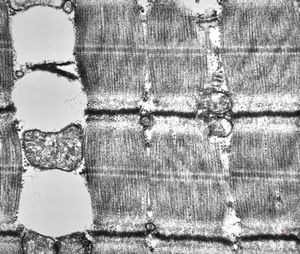

F,25y. | myopathy - atrophic and regenerating muscle cells